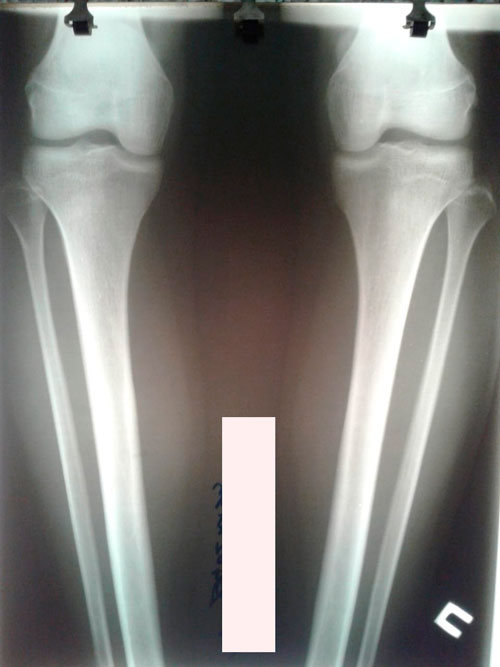

Исходник - 22 года. Усть -Каменогорск

Дата операции 08.11.2018г.

Ротация с обеих сторон.

IMG-20181107-WA0011.jpg

IMG-20181107-WA0010.jpg